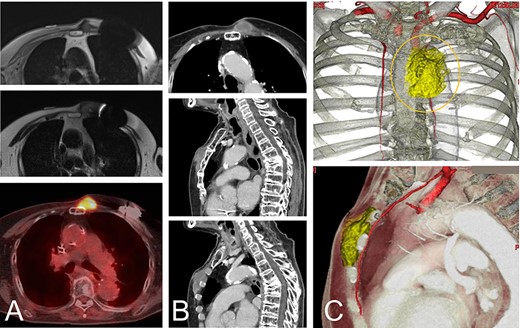

A magnetic resonance image (MRI) and computed tomography (CT) showed the chest wall lesion on the surface of the sternum and the distal third rib. The tumor size was 4 x 5 cm, and the lesion extended to the subcutaneous tissue and intracoastal spaces between the second and third ribs (Fig. 1). The histologic evaluation of a biopsy specimen was characterized as proliferation of atypical spindle cells.

An 82-year-old woman with a malignant spindle cell sarcoma in the superficial chest wall. The MRI shows a lesion involving the anterior sternum on the left side with low-to-intermediate signal intensity on T1- (A-top) and T2-weighted images (A-middle) with a high SUVmax on FDG-PET (A-bottom). CT with contrast medium depicted the lesion (B). The lesion involved not only the anterior sternum (B-top and -middle), but also the intercostal space (B-bottom). The cut line (orange line) is drawn with a yellow line. The internal thoracic artery runs under the tumor and the vessels were resected together (C).